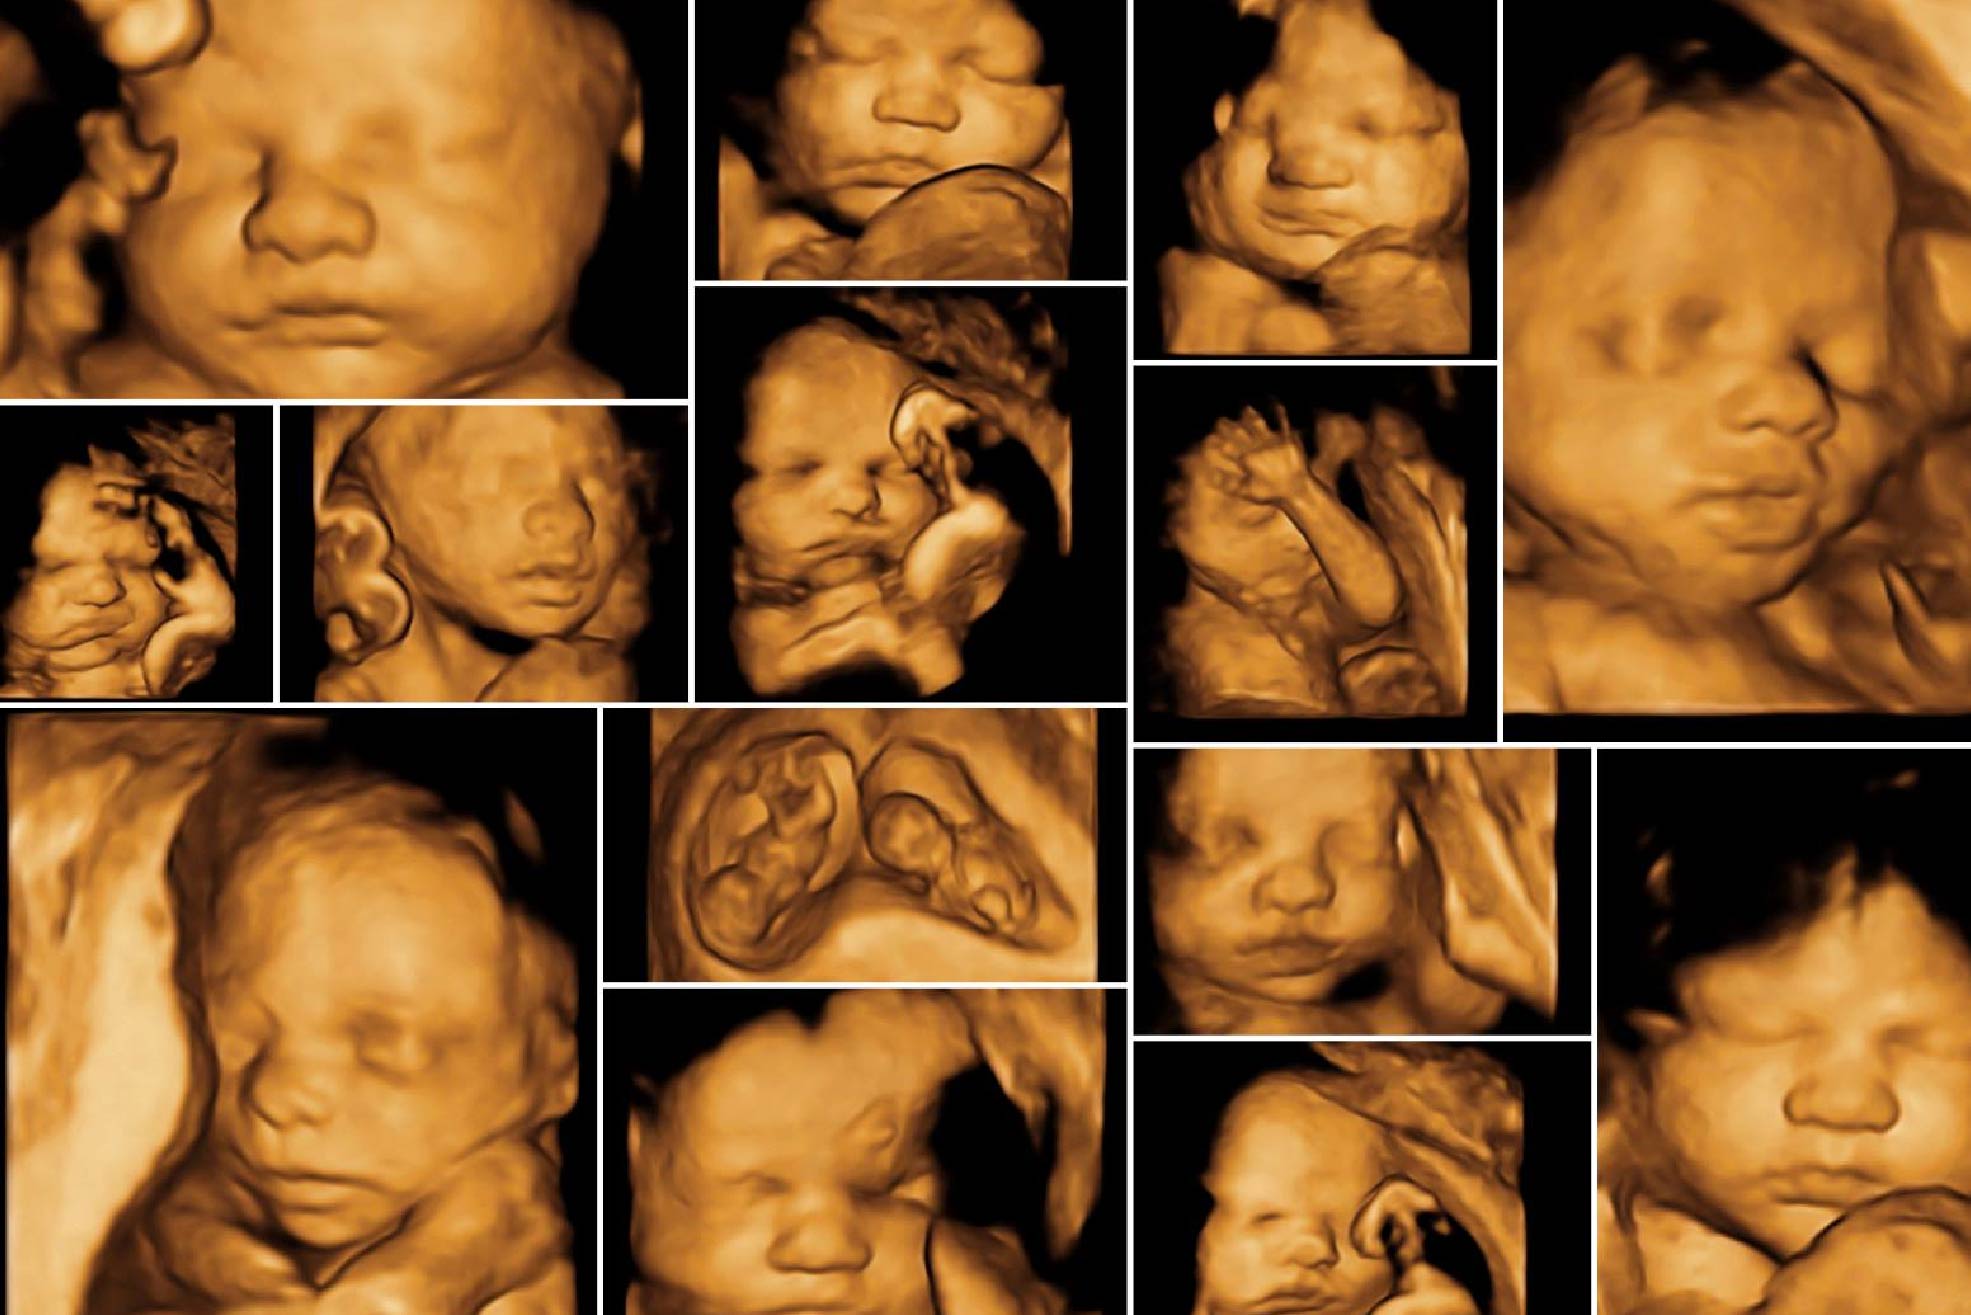

Ultrassom 3D e 4D

Proporciona imagens detalhadas do bebê em três dimensões (3D) e em tempo real (4D), permitindo que os pais visualizem com mais nitidez os traços do rosto e movimentos do bebê.

• Ultrassom convencional (2D): Exame básico que mostra imagens em preto e branco do bebê.

• Ultrassom 3D: Exibe imagens tridimensionais mais detalhadas.

• Ultrassom 4D: Mostra o bebê em movimento em tempo real, permitindo visualizar expressões faciais e movimentos.